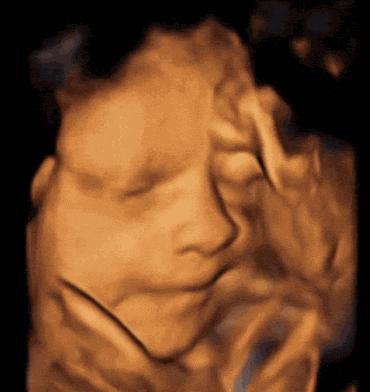

虽然四维彩超已经是目前最先进的技术了,不仅可以检查胎儿的发育情况,还可以实时看到胎宝宝的各种动作,但这还是无法检查出胎儿所有的畸形,存在一定的局限性。

四维彩超的检查时间一般在怀孕5~6个月左右,距离预产期还有4~5个月的时间,这期间宝宝还会继续生长发育,这是一个动态的过程,也就是说,只要胎儿在发育,就有可能出现异常的情况。